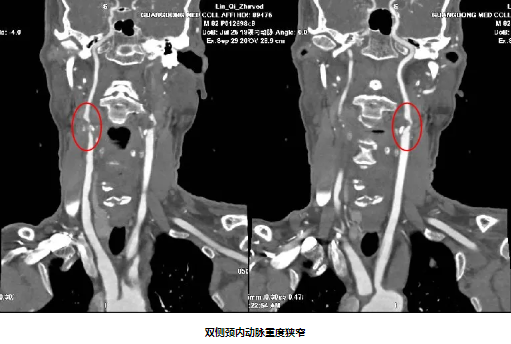

82岁男性,因“双下肢无力10天”入院,既往有“高血压病”史10年。入院后完善颈动脉彩超及影像学检查提示:1.分水岭梗死(双侧皮质下型)2.双侧颈内动脉重度狭窄 3.窦性心动过缓。经颈动脉狭窄MDT团队充分讨论,精心安排,在心血管内科中心的协助下,脑血管病专科团队克服了患者高龄、心动过缓等危险因素,成功给予患者双侧颈动脉支架同期植入,患者症状得到明显好转。